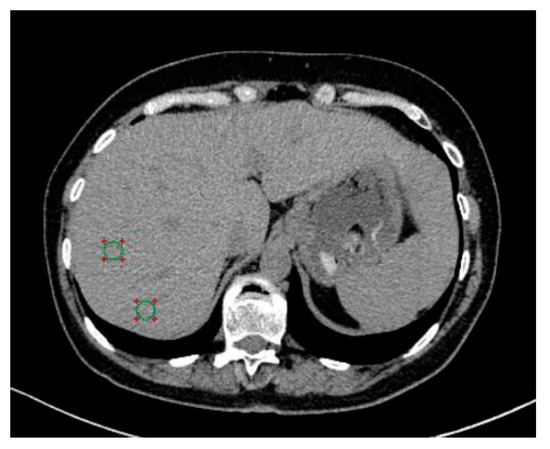

2.2. CT Protocol and Image Analysis